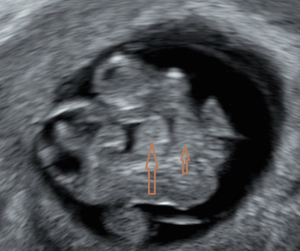

Chief complaint: a 27-year-old gravida presented for routine prenatal ultrasonographic evaluation. Early first-trimester ultrasound surveillance (6 weeks) revealed unremarkable fetal development. The patient denied any pregnancy-associated discomfort at this stage. History: bilateral salpingectomy performed. Personal and family history: the patient had no significant family or genetic history. Physical examination revealed no remarkable findings. All laboratory parameters fell within established normal limits. The patient used ART due to tubal factors. On 16 June 2024, the patient underwent a frozen-thawed blastocyst transfer. The two-dimensional (2D) ultrasound examination at 6 weeks of pregnancy showed a gestational sac in the uterine cavity, with a yolk sac inside and a 0.52 cm-long fetal bud close to the yolk sac, which showed a faint primitive heart tube pulsation. Ultrasound examination at 8 weeks of pregnancy showed a gestational sac in the uterine cavity, with one yolk sac, an amniotic sac, and two fetuses in the gestational sac. One fetus had a crown-rump length of 2.03 cm, and the other fetus had a crown-rump length of 1.88 cm. Both fetuses were consistent with an 8-week pregnancy. Both fetuses demonstrated complete thoracic ectopia cordis with anterior protrusion and cardiac fusion. The sagittal section showed that the two fetuses had a “ball-holding” sign, with a common heartbeat of 169 bpm (Figure 1). The organs above the umbilical part of the two fetuses were connected and protruded towards the front of the abdomen, with a cover on the surface. The cross-section of the chest showed that the two fetuses showed a “dumbbell” sign (Figure 2). The umbilical cords of the two fetuses were fused into a thick umbilical cord, and the entrance end of the umbilical cord abdominal wall was inserted into the fusion of the umbilical cord. The distal end of the umbilical cord was bifurcated and inserted into the placental parenchyma, respectively. Three-dimensional (3D) ultrasound surface imaging intuitively showed the relative positional relationship between the two fetuses and the exposure of the conjoined twins to the heart that fused each other on the outside of the chest cavity (Figure 3). Due to the early gestational week, the anterior diaphragmatic midline of the two fetuses was unclear. The ultrasound machine used in this case was a GE Voluson E10 (GE Healthcare, Chicago, IL, USA), with a RIC5-9-D probe. Figures 4,5 show normal fetus control images at the same gestational age.

With the widespread application of high-resolution transvaginal ultrasound, visualization of early pregnancy has become possible. The accuracy of assessing the risk of fetal chromosomal abnormalities through early pregnancy ultrasound combined with biochemical markers has improved, leading to the diagnosis of more fetal abnormalities in the early stages of pregnancy. A study indicated that ultrasound diagnosis of conjoined twins typically occurs between 11 and 13 weeks and 6 days. Screening at this stage can detect the most severe fetal malformations (8). There are reports that high-resolution ultrasound has advanced the diagnosis of conjoined twins to 7 weeks of gestation. However, due to the early gestational age, it is difficult to precisely determine the specific type of connection between the twins, and color Doppler ultrasound is typically required to assist in diagnosing the presence of conjoined twins (9). Fetal development is a process, and it can only be detected by ultrasound once it has reached a distinguishable gestational age. When fetal activity increases, around 8 weeks of gestation, it becomes easier to distinguish between monochorionic twins and conjoined twins (10). The patient underwent an ultrasound examination at 6 weeks of gestation, during which only a small, short, line-like embryonic bud and weak fetal heartbeat were observed. During the ultrasound examination at 8 weeks of gestation, we discovered that the two fetuses were embracing a “spherical” structure. The sagittal section revealed the “ball-holding” sign, and the transverse section showed a notch at the junction of the thoracic and abdominal walls, presenting the “dumbbell” sign. These two signs are specific to thoracoabdominal conjoined twins, with both fetuses affected by Cantrell’s pentalogy. Transvaginal 2D and 3D ultrasound provides direct evidence for the early identification of a special type of conjoined twins and advances the diagnostic gestational age to 8 weeks. Through transvaginal 2D ultrasound, the issue was identified, followed by adjusting the probe direction and angle to locate the specific connection site of the conjoined twins and determine the type of connection. The multiplanar views of 3D ultrasound provide additional detailed information. Adjusting the direction of light incidence, rotating the probe at multiple angles, and adjusting the 3D image, combined with surface imaging mode, yields more detailed features. The combination of 2D and 3D ultrasound provides more information than 2D ultrasound alone, offering more intuitive images, particularly suitable for fetuses with abnormal external features. A study has confirmed the role of 3D ultrasound in diagnosing prenatal abnormalities, which is consistent with our findings (11).

Ventral body wall defects represent a spectrum of malformations, likely caused by disrupted mesodermal development during early embryogenesis (days 14–19), followed by failed diaphragmatic crossing (12). These defects arise from abnormal closure of the ventral body wall folds and are present in various combinations, the most severe of which is Cantrell’s pentalogy. First described by Cantrell et al. in 1958, this syndrome comprises five congenital anomalies: cardiac, pericardial, sternal, diaphragmatic, and anterior abdominal wall defects, with an estimated incidence of 1 in 65,000 to 1 in 200,000 live births (4). The hallmark features of Cantrell’s pentalogy are ectopia cordis and omphalocele. Thoraco-abdominal schisis manifests as partial or complete displacement of the heart out of the thoracic cavity. An omphalocele is another common manifestation, wherein the abdominal contents protrude through the anterior abdominal wall, covered by a thin membrane. Sternal defects may present as a partial or complete absence of the xiphoid process of the sternum. Diaphragmatic defects involve congenital or acquired fissures in the diaphragmatic structure. Although pericardial defects are generally less severe and rarely life-threatening, they may occasionally lead to complications such as pericardial effusion. Cardiac defects such as atrial septal defect, transposition of the great arteries, pulmonary valve stenosis, and tetralogy of Fallot are associated with Cantrell’s pentalogy. Some researchers classify Cantrell’s pentalogy into three types based on the type of defect: (I) complete syndrome involving all five defects; (II) four defects including the sternum and anterior chest wall; and (III) incomplete type involving various combinations of defects, including sternal abnormalities (13). The ultrasound examination of this case revealed significant cardiac ectopia and omphalocele. The shared heart and abdominal organs of the two fetuses were fused and protruded through the thoracic wall toward the anterior thoracoabdominal wall. The sternum was not visible. The early stage of gestation precluded definitive characterization of the specific diaphragmatic and cardiac malformations. Cardiac ectopia, omphalocele, thoraco-abdominal schisis, and an unseen sternum showed direct signs of conjoined twins, and both fetuses were associated with incomplete Cantrell’s pentalogy. A key limitation in early prenatal diagnosis of conjoined twins with Cantrell’s pentalogy is the early gestational age, when incomplete fetal organ development may obscure the detection of associated structural abnormalities.